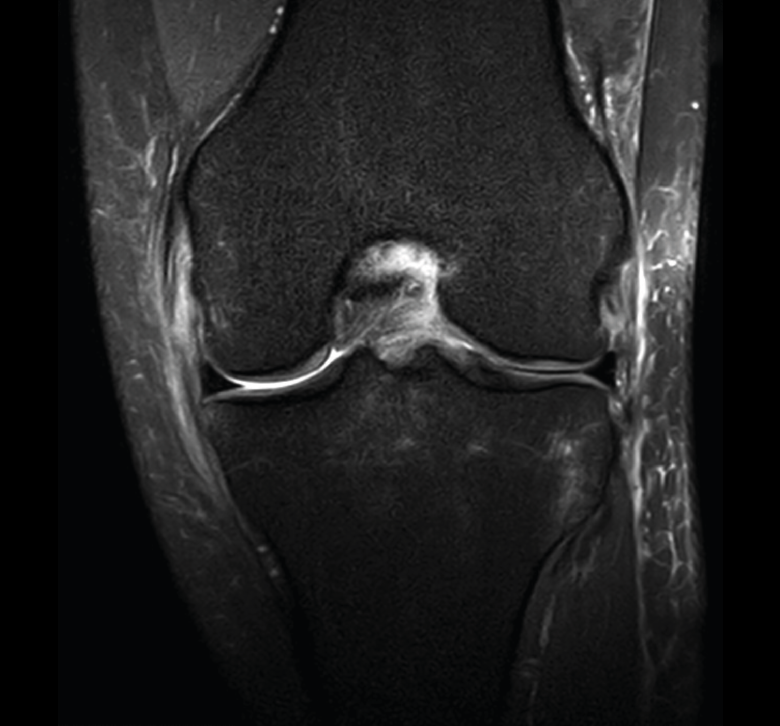

Figura 35. Corte de secuencia coronal y sagital de resonancia magnética de rodilla: rotura en asa de cubo del menisco interno con fragmento desplazado al intercóndilo.